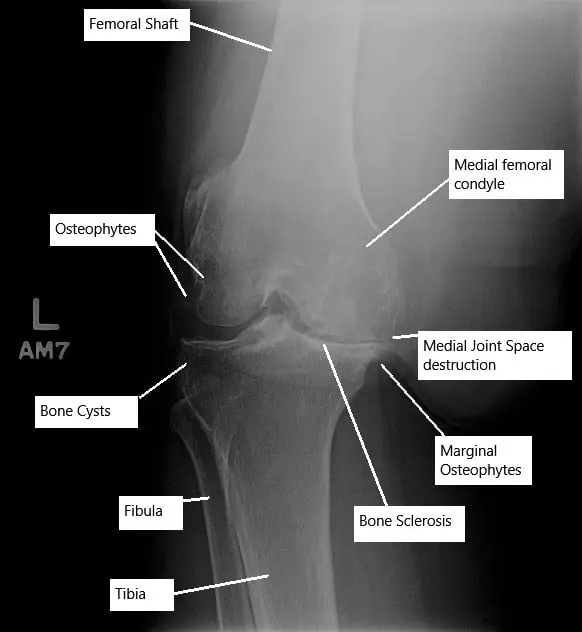

In the early stage of osteoarthritis, there is swelling of the articular cartilage, there is the appearance of fissures and cracks in the articular cartilage. The body attempts to repair it by increasing blood supply with the formation of new blood vessels. The new blood vessels invade the subchondral bone which leads to its increased density.

The destruction of the cartilage continues leading to decreased joint space visible on radiographs of large joints. The degenerated cartilage either dissolves in the joint or forms ‘’loose bodies’’ inside the joint. T

he body tries to repair the exposed bone resulting from the denuded cartilage. The repair leads to thickening and overgrowth of the subchondral bone. The thickening of the subchondral bone is especially prominent at the sides of the joint which appear as bone spurs.

The synovial membrane of the joint undergoes hyperplasia, which is swollen and inflamed. There is a development of cysts/cavities in the subchondral bone at the places of maximum stress. The pressure inside the joint increases as a result of decreased venous outflow and an increased arterial flow in the subchondral region. The increased pressure leads to the symptoms of pain at rest.

Plain radiographs are usually the first radiological test done to look for joint space reduction, cysts, and thickening bones. In some cases, for a detailed evaluation, a CT scan or an MRI may be ordered. An MRI gives the details of all the soft tissue structures inside the joint, which are not visible on an X-ray.